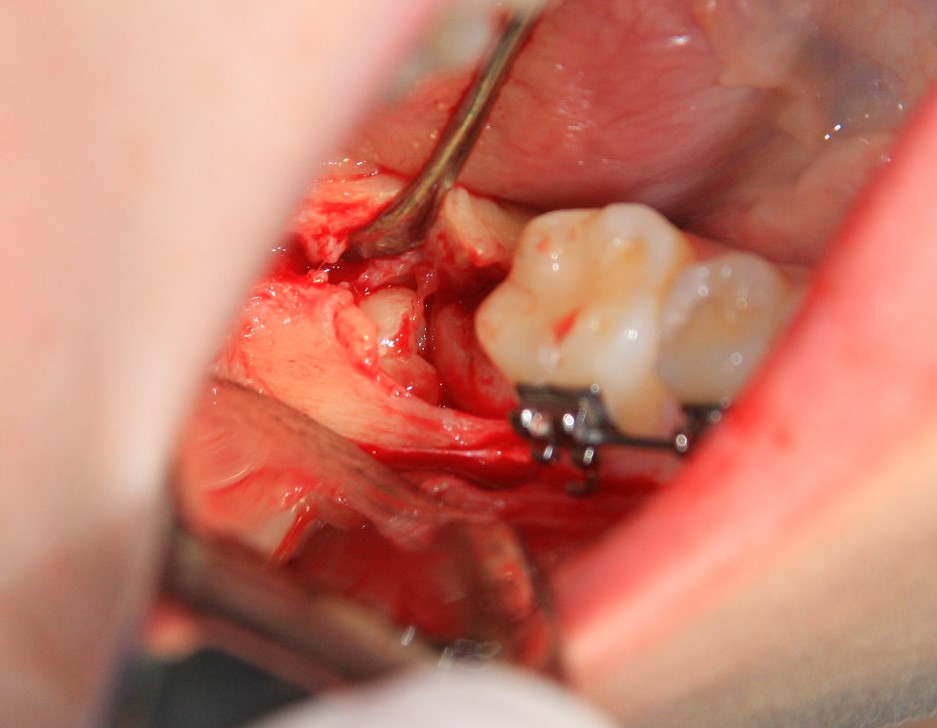

Далее, разрез. Создаем доступ к зубу. Для этого используется повышающий наконечник с соответствующими фрезами. Вот они, восьмерка и семерка:

Чтобы аккуратно удалить восьмерку и не повредить соседний зуб, мы делим ее на две части. НИКАКИХ МОЛОТКОВ И ДОЛОТОВ))) Все делается, исключительно, с помощью фрез:

После чего аккуратно удаляем коронку:

А через минуту — и корни зуба. Поверьте, это очень просто, для этого не нужно прилагать каких-то усилий. Достаточно просто включить голову.